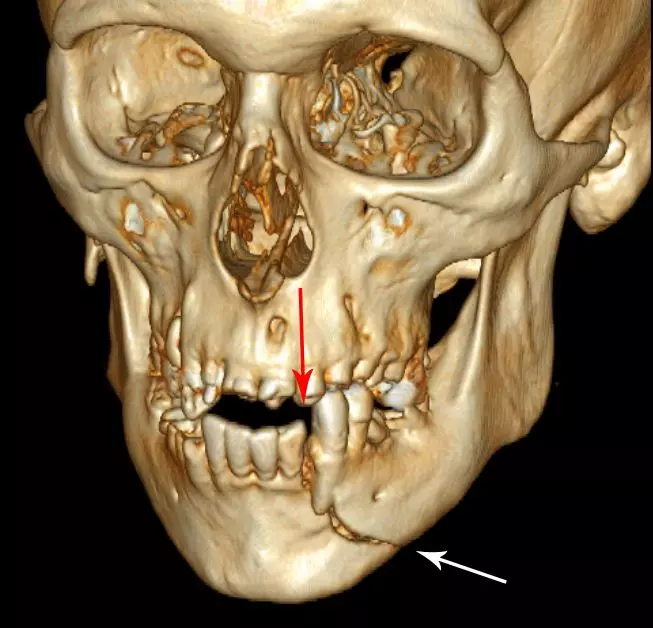

- Maxillofacial trauma

Image - 3D CT reconstruction showing a fracture through the body of the mandible

Creative commons source by Coronation Dental Specialty Group [CC BY-SA 4.0 (https://creativecommons.org/licenses/by-sa/4.0)]